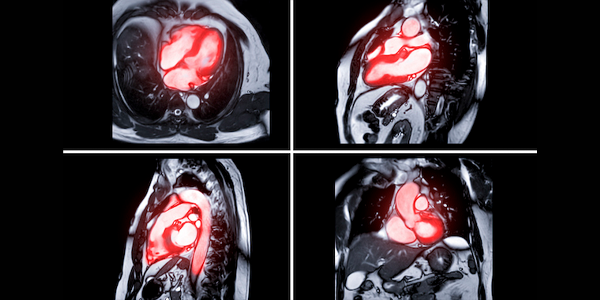

Kardiyak MR, kalbinizin yapısını ve fonksiyonunu detaylı bir şekilde değerlendirmek için kullanılan gelişmiş bir görüntüleme tekniğidir. Bu yöntemde, güçlü manyetik alanlar ve radyo dalgaları kullanılarak kalbinizin yüksek çözünürlüklü görüntüleri elde edilir. Kardiyak MR, kalp kasının yapısını, kalp kapakçıklarının işlevini, kan akışını ve kalbin pompalama gücünü değerlendirmede kullanılır. Bu sayede, birçok kalp hastalığının teşhisi ve tedavi planlaması daha etkin bir şekilde yapılabilir.

Kardiyak MR, kalbin yapısını ve fonksiyonunu detaylı bir şekilde değerlendirmek için kullanılan gelişmiş bir görüntüleme tekniğidir. Bu yöntemde, güçlü manyetik alanlar ve radyo dalgaları kullanılarak kalbin yüksek çözünürlüklü görüntüleri elde edilir. Kardiyak MR, kalp kasının yapısını, kalp kapakçıklarının işlevini, kan akışını ve kalbin pompalama gücünü değerlendirmede kullanılır. Bu sayede, birçok kalp hastalığının teşhisi ve tedavi planlaması daha etkin bir şekilde yapılabilir.